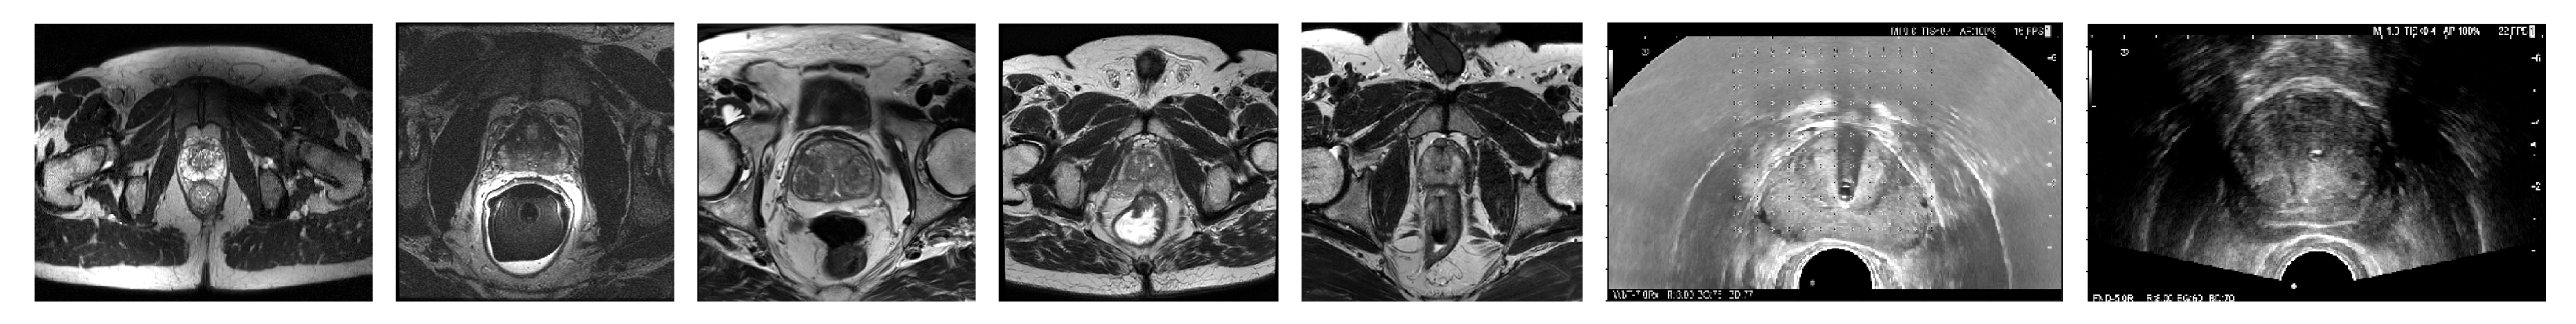

Regarding exclusion criteria, before separating the images into any subsets, all segmentations were examined and those with obvious errors were directly excluded. Therefore, no corrections were made, so as to better preserve the particular criteria from each expert (except for the “Private” dataset, in which all segmentations were revised). The number of samples (N) in Table 1 is computed after this filtering. As a special mention, 18 images from “Prostate-3T”, which were also present in “Promise12” or “Promise12_test” (although with different GT segmentations), were also discarded; and other 30 images from “Prostate-3T” (half of the original dataset), which systematically left many slices in the base and apex unsegmented, had to be discarded as well. Figure 1 shows the center slice of a sample from each of the datasets.

For the 3D-US segmentation model, two different datasets were employed: “IVO” and “Private”, both coming from the same institutions as their homonymous MR datasets. For “IVO” ( N = 160 images), five different urologists with six to thirty years of experience segmented the images, while for “Private” ( N = 82 images), it was two urologists with more than ten years of experience; no exclusion criteria were applied. Images from both datasets were captured using Hitachi scanners at spacings of 0.20 mm to 0.41 mm in any axis. Figure 1 shows the center slice of a sample from each axis. Unfortunately, no further segmented datasets were found on the Internet for this image modality.

Figure 1. Center slice of a sample from MR and US datasets (from left to right): “Girona”, “Promise12”, “Prostate-3T”, “IVO (MR)”, “Private (MR)”, “IVO (US)” and “Private (US)”.